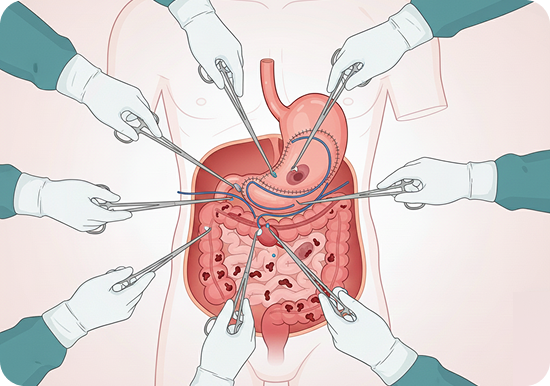

Advanced Minimal Access Surgery

- Laparoscopic and robotic gastrointestinal surgeries

- Keyhole surgery for hernia repairs (inguinal, incisional, and diaphragmatic hernias)